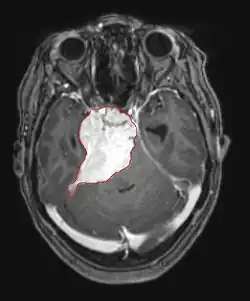

Počítačová tomografie (CT) a magnetická rezonance (MRI) mohou účinně detekovat neoplazii v mozku. MRI je citlivější než CT pro identifikaci lézí, ale má kontraindikace pro pacienty s kardiostimulátory, nekompatibilními protézami, kovovými svorkami a dalšími. CT zůstává metodou volby k detekci kalcifikací v lézích nebo kostních erozích lebky nebo spodiny. Použití kontrastních látek, které jsou v případě CT jodované a v případě MRI paramagnetické ( gadolinium ), umožňuje získat informace o vaskularizaci a integritě hematoencefalické bariéry, lepší definici nádorového nádoru ve srovnání k okolnímu edému a generování hypotéz o stupni malignity. Radiologické vyšetření také umožňuje posouzení mechanických účinků a následných změn v mozkových strukturách vyplývajících z nádoru, jako je hydrocefalus a kýla, jejichž účinky mohou být fatální. Konečně, v rámci přípravy na operaci, může být tato diagnostika použita k určení umístění léze nebo infiltrace nádoru do životně důležitých oblastí mozku. Pro tento účel je MRI účinnější než CT, protože může poskytovat trojrozměrné obrazy.

Diagnostické radiologické zobrazovací nástroje zdůrazňují změnu neoplastické tkáně ve srovnání s normálním mozkovým parenchymem (prostřednictvím změn v elektronicky zobrazené hustotě tkáně na CT a intenzitě signálu na MRI). Jako většina patologických tkání jsou nádory také rozpoznatelné podle zvýšené akumulace intracelulární vody. Na počítačovém tomogramu se jeví hypodenzní, tj. s menší hustotou než mozkový parenchym, na tomogramu nukleární magnetické rezonance s relaxací spin-mřížky hypointenzivní a při spin-spin relaxaci stejně jako protonové vážení (PD) hyperintenzivní.

V nádorové tkáni je obecně větší podíl zvýšení kontrastu způsoben konkrétní hematonádorovou bariérou, která umožňuje průchod jódu (CT) a gadolinia (MRI) do intratumorálního extravaskulárního intersticiálního prostoru. To zvyšuje signál (hustotu nebo intenzitu) nádoru. Je však třeba dbát na to, aby zvýšení kontrastu definitivně neodlišilo neoplazii od edému v okolí rány. Ve skutečnosti anatomicko-patologický nález v maligní infiltrující nádorové tkáni gliomu, jako u glioblastomu a anaplastického astrocytomu, se také projevuje mimo vazogenní edém způsobený destrukcí hematoencefalické bariéry nádorem. Poslední klinický stav je špatně detekovatelný diagnostickým zobrazením.

Na -MRI ukazuje intrakraniální tumor jako masivní lézi, která se po použití kontrastní látky může stát více luminiscenční. Vždy však dojde k anomálii signálu -Magnetická rezonance, která indikuje přítomnost neoplazie nebo vazogenního edému. Obvykle zvýšená luminiscence (zesílení kontrastu) svědčí pro nádor vyššího stupně malignity. Pro glioblastom je charakteristický kontrastní prstenec, jehož luminiscenční část odpovídá vitální části maligního nádoru a tmavší -hypointense oblast odpovídající nekróze tkáně.

Mozkové metastázy jsou nejčastějšími intrakraniálními novotvary u dospělých, jsou desetkrát častější než primární mozkové nádory. Krokují na 20 do 40 procenta dospělých s rakovinou a jsou spojeny hlavně s rakovinou plic a prsu a melanomem. Tyto léze jsou výsledkem šíření rakovinných buněk krevním řečištěm a nejčastěji se vyskytují na křižovatce šedé a bílé hmoty, kde se mění průřez krevních cév a zachycují embolie nádorových buněk. 80 procento lézí se vyskytuje v mozkových hemisférách, 15 procenta v mozečku a 5 procent v mozkovém kmeni. Asi 80 procento pacientů má v anamnéze systémovou rakovinu a 70 procento má četné mozkové metastázy.

V diagnostice a léčbě těchto lézí bylo nedávno dosaženo významného pokroku, jehož výsledkem je lepší přežití a kontrola symptomů. Nástup známek a symptomů je podobný jako u jiných masivních lézí v mozku. Diagnostickou metodou volby je magnetická rezonance s použitím kontrastních látek.